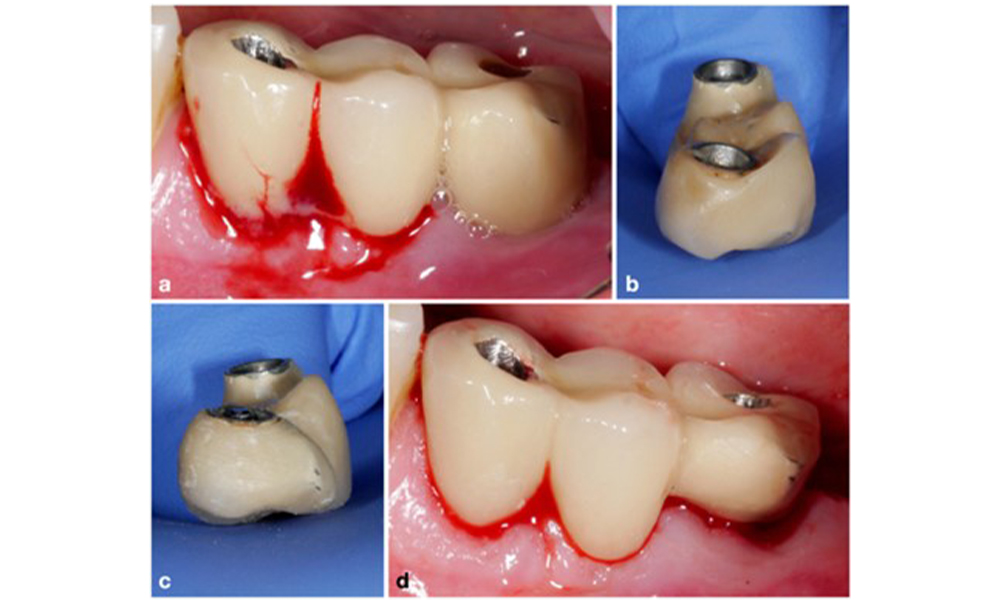

Pour les implants dont la surface est modifiée et dans les régions où la régénération osseuse est improbable, l'implantoplastie doit être envisagée. Cette procédure consiste à retirer les fils de l'implant et à lisser la surface micro-structurée de l'implant à l'aide d'instruments rotatifs (figure 12). Cette approche facilite la décontamination complète de la surface de l'implant et, surtout, améliore le contrôle du biofilm postopératoire (Bertl et Stavropoulus 2021 ; El Chaar et al. 2020 ; Geremias et al. 2017). Faute de preuves cliniques suffisantes, le rôle de l'implantoplastie est controversé (Herrera et al. 2023 ; Ramanauskaite et al. 2021), mais les craintes concernant l'induction d'une inflammation par le dépôt inévitable de particules de titane et le risque accru de fracture de l'implant en raison de la réduction de sa résistance n'ont pas été étayées (Stavropoulos et al. 2019).

Pour les implants dont la surface est modifiée dans les zones où la régénération osseuse est limitée, l'implantoplastie doit être envisagée. Dans un cas de déhiscence buccale, l'aspect buccal de la surface modifiée de l'implant (a) a fait l'objet d'une implantoplastie (b-d), les tissus environnants étant couverts pour minimiser la contamination par les particules de titane, à l'aide d'une gaze et d'une digue en caoutchouc liquide.

Figure 12. Pour les implants dont la surface est modifiée dans les zones où la régénération osseuse est limitée, l'implantoplastie doit être envisagée. Dans un cas de déhiscence buccale, l'aspect buccal de la surface modifiée de l'implant (a) a fait l'objet d'une implantoplastie (b-d), les tissus environnants étant couverts pour minimiser la contamination par les particules de titane, à l'aide d'une gaze et d'une digue en caoutchouc liquide.